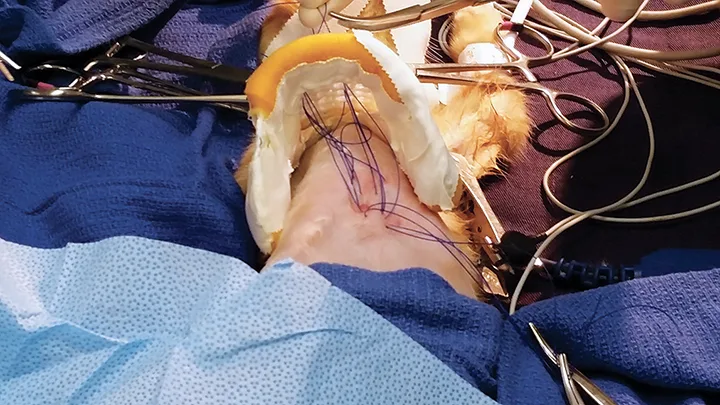

A lateral thoracic radiograph of a cat with an abnormal sternum.

FIGURE 1

Pectus excavatum in a 12-week-old kitten. The caudal sternebrae are deviated dorsally, whereas the xiphoid process is pointed ventrally.

Diagnosis is based on physical examination and thoracic radiography findings (Figure 1). Radiographs should show a sternal deformity and decreased caudal thoracic space secondary to dorsal deviation of the sternum.3,5 The severity of the deformity can be graded using 2 indices (ie, vertebral or frontosagittal; see Deformity Indices), although these indices may not correlate with the severity of clinical signs.4 Severity can also be evaluated with CT. A study in kittens found CT to be useful in identifying midline sternal deviation that could potentially cause more severe clinical signs, despite relatively mild skeletal deformity, because of diastolic restriction.4